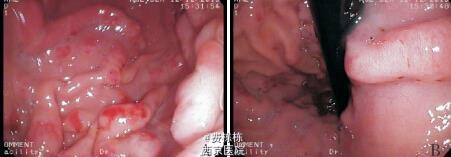

入院后给予抗感染(更昔洛韦、头孢美唑)、输注白蛋白(总量 1 g/kg,入院 1 周内分 3 次输注)及利尿等治疗,患儿水肿消退,腹痛及呕吐缓解 ,颈部淋巴结缩小,扁桃体分泌物消失。进一步行全身麻醉下电子胃镜及结肠镜检查,发现胃底及胃体黏膜明显充血水肿,呈结节样肥厚、隆起,其表面可见糜烂,质脆易出血,较多白色黏液覆盖黏膜表面;食管、贲门、胃窦、胃角、幽门、十二指肠球部未见异常。结肠镜检查未见异常。取胃窦及胃体黏膜活检,提示胃窦黏膜组织呈慢性炎症改变,嗜酸粒细胞约 1 个 /HPF;胃体黏膜上皮呈管状腺瘤样增生,固有膜及黏膜下层水肿明显,并见散在的炎性细胞浸润,嗜酸粒细胞最多约 15 个 /HPF,免疫组化检查示幽门螺杆菌(Hp)阴性,CMV 阴性。之后给予洛赛克抑酸、吉法酯保护胃黏膜等治疗。入院后第 16 天复查肝功能全套(9 项)TP 64.4 g/L,ALB 35.8 g/L,GLB 28.6 g/L,均较入院时升高,白蛋白仍低于正常值,电解质及血液分析未见异常。入院第 26 天在全麻下行超声胃镜检查,提示胃体可见多处的第二层无回声性增厚,最厚处达 5.8 mm,胃部周围未见明显增大的淋巴结。考虑诊断“蛋白丢失性胃病”(protein-losing gastropathy, - PLG)。